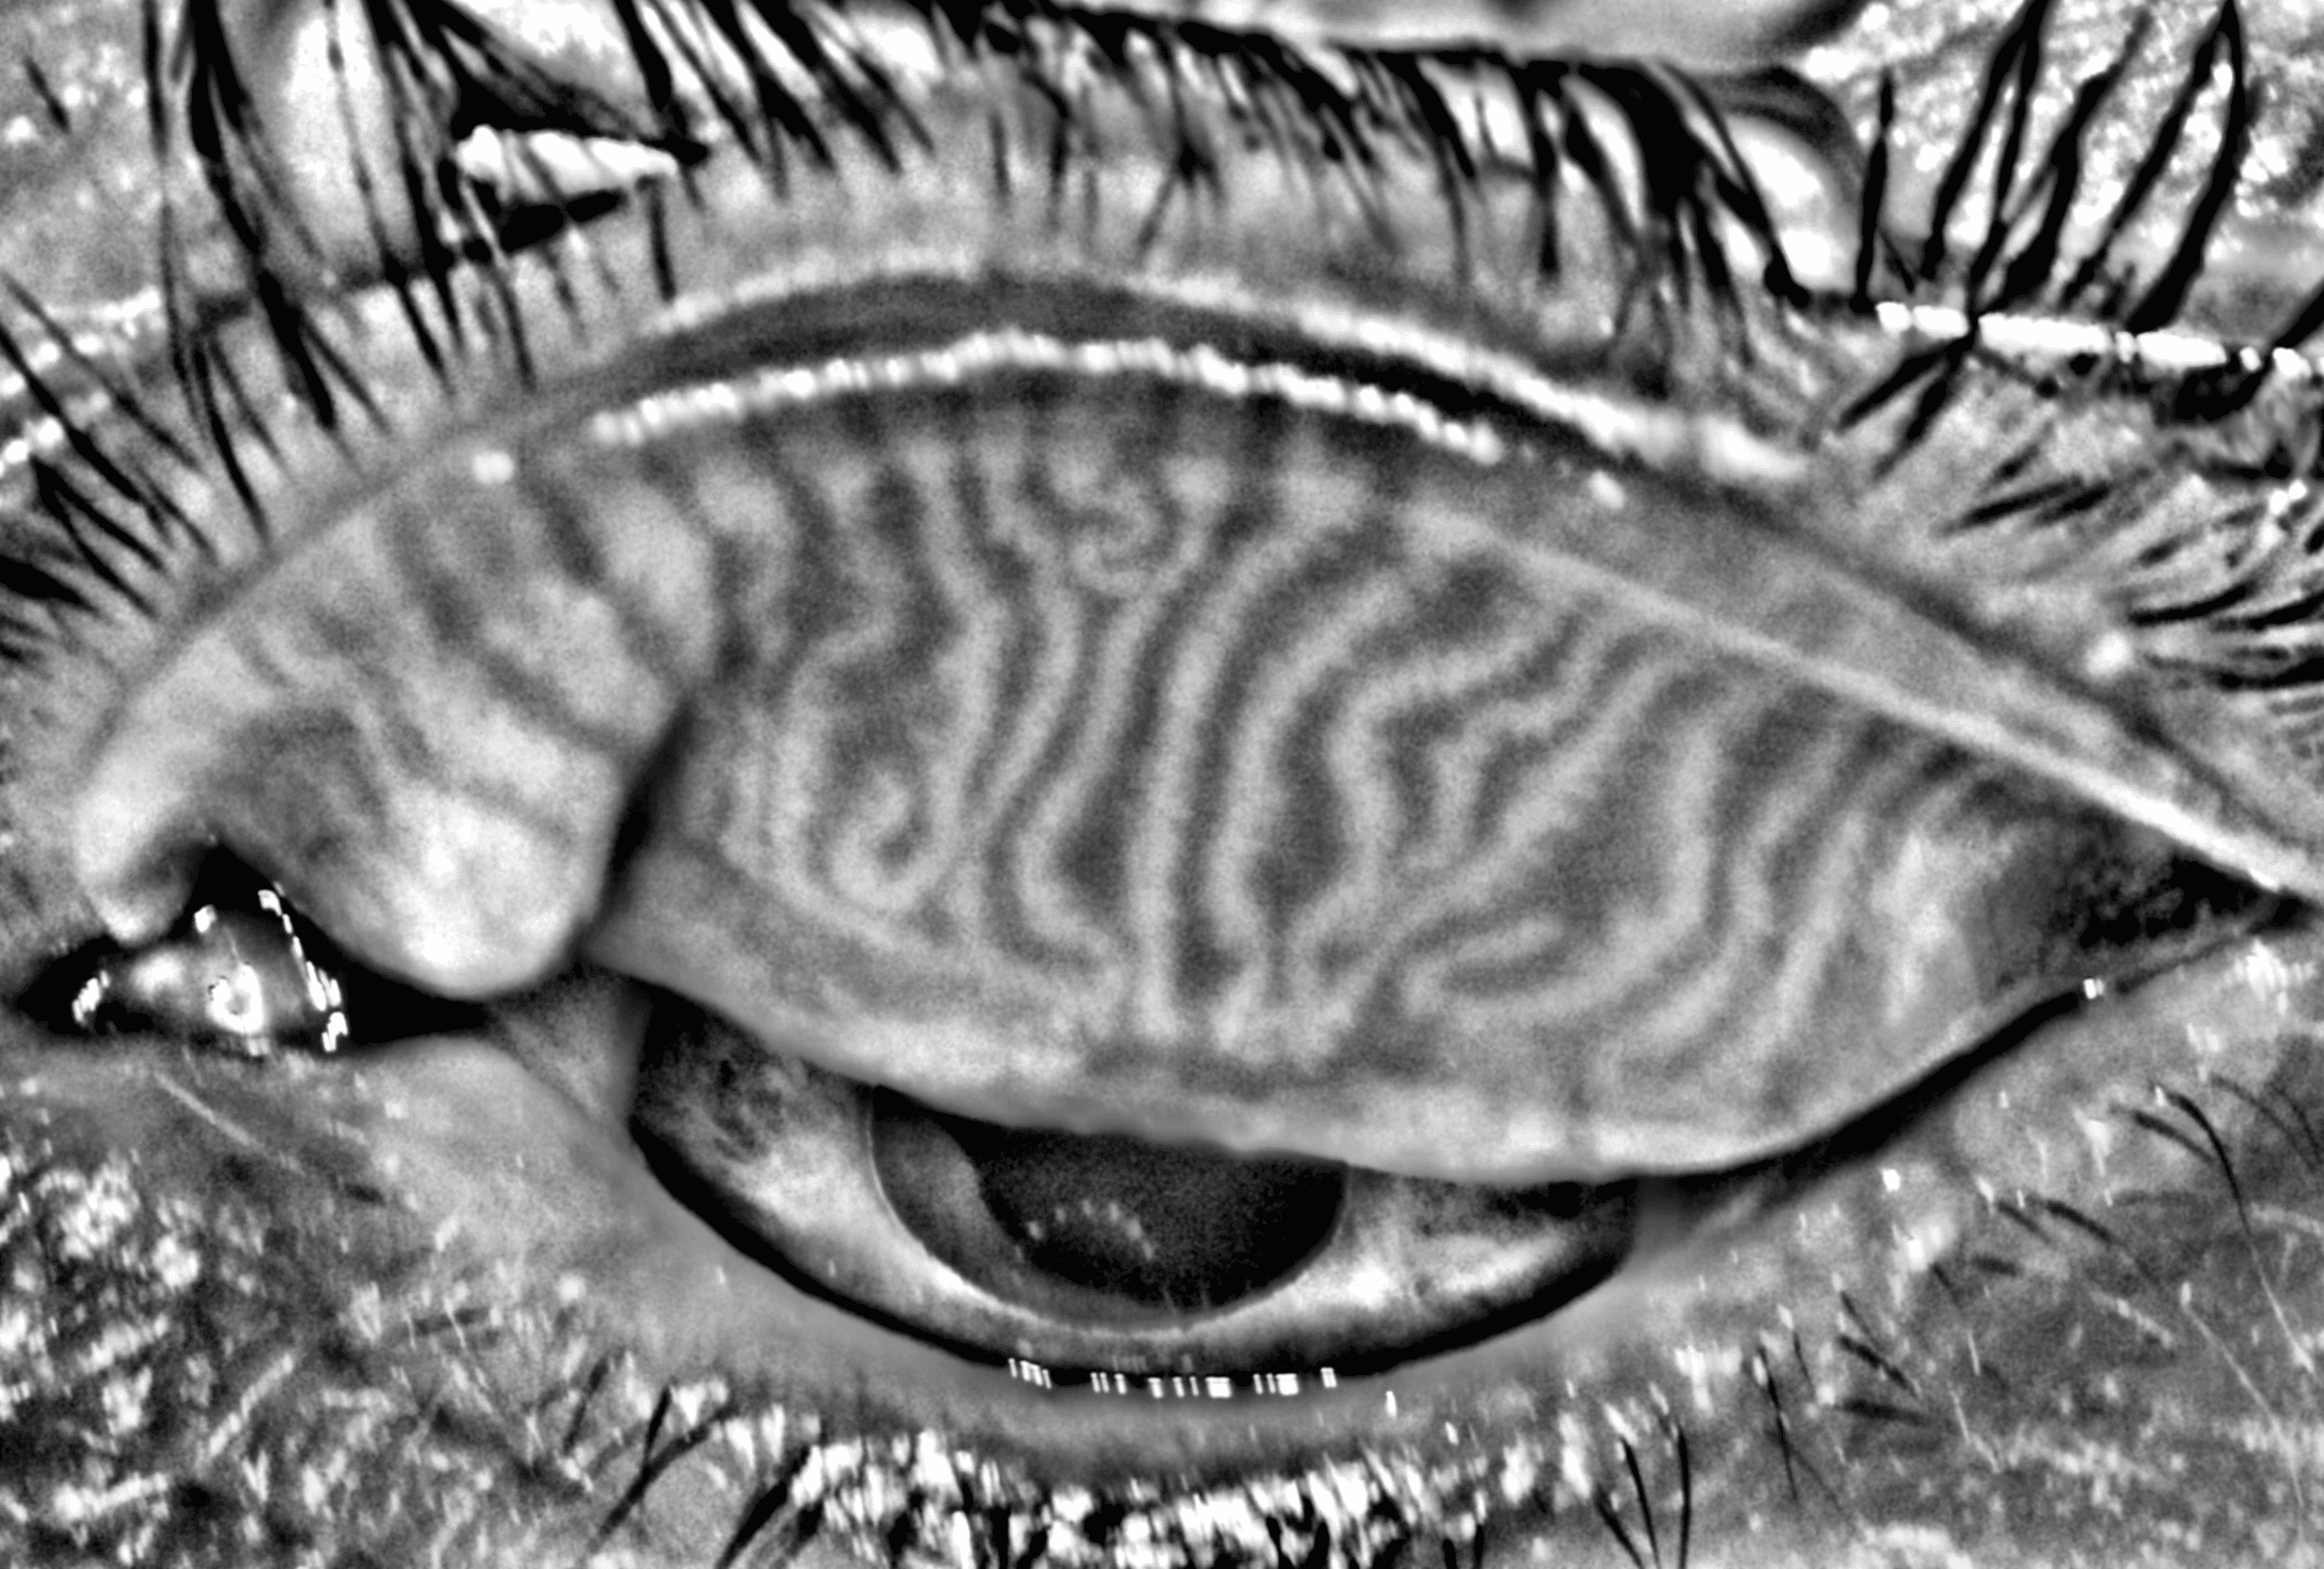

Capture and visualize meibomian gland structure, blink dynamics, tear film appearance, fluorescein imaging, and patient-reported symptoms using a single, compact device designed to integrate seamlessly into existing clinical setups.

AI-Enhanced Visualization

See More with AI-Assisted

Real-Time Visualization

AI-assisted image processing enhances the visibility of ocular surface features, reducing time required manual image adjustments and allowing clinicians to focus on efficient clinical review. Operating directly on the live video stream, it provides immediate visual feedback that supports faster alignment, more confident image capture, and a smoother workflow.